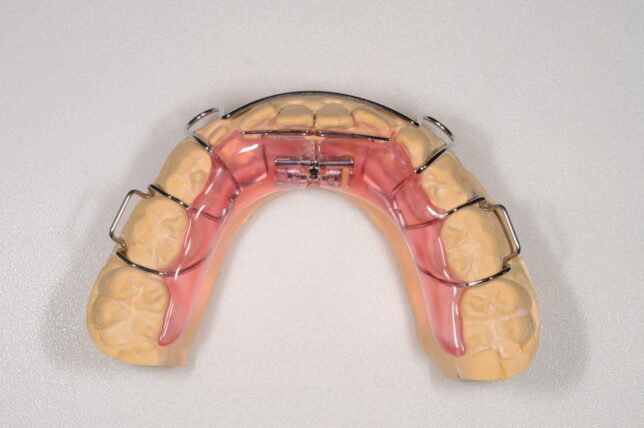

当院がおこなっている子どもの矯正治療↓